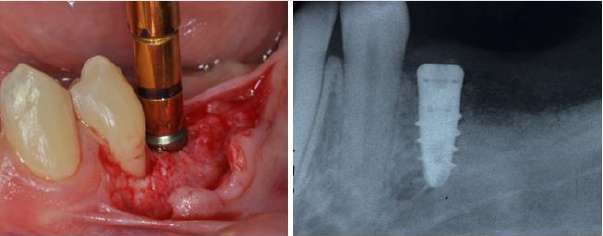

Once the graft was completed the buccal and lingual flaps were extended through a brushing technique with an apico coronal movement of the periosteal elevator and the cortical lamina was cut, shaped and adjusted to fit the area (Figure 8) Flaps were than secured with 4.0 Vicryl absorbable sutures to secure an uneventful healing (Figure 9). Post-operative instructions included use of Amoxicillin (Augmentin 1 gr. X day for 7 days) and antiinflammatory on demand. Six months after bone augmentation the ridge had a new shape allowing the placement of a standard 4.1 diameter dental implant.

(Biaggini Medical Devices, Arcola, Italy), the ridge showed now a width of 7 mm as compared to the 2 mm at baseline (Figure 10). Three months later the implant was exposed and a healing abutment was connected associating and apical repositioned flap in order to replace the keratinized gingiva buccal to the abutment (Figure 11) One month after complete maturation of the soft tissue impressions were taken in order to fabricate a ceramic crown (Figure 12). Final restoration was delivered about nine months after the beginning of treatment (Figures 13&14) but the radiograph and the clinical picture show how the primary objectives of treatment were met. Bone augmentation in order to accommodate a standard diameter implant in order to re-establish function and proper occlusion. A three year follow up shows a perfect stability of the regenerated area (Figure 15) [5].